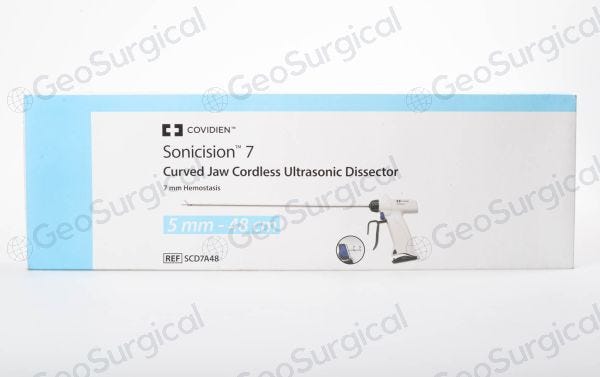

HistoSonics、世界初の「Edison®ヒストトリプシー・システム。SONOBIO Split-type Ultrasonic Homogenizer/Sonicator。Model 3000 - Ultrasonic Homogenizers - Sonicators。ミルキークイーン令和6年兵庫県産玄米15kg。PACIFIC BIOSCIENCE LABORATORIES クラリソニック(ホワイト)数回使用後、自宅保存していた中古品です。★ コメントからご相談ください-----------------------------------------・バラ売り可能・他の出品商品とまとめ買いでお値引き可能★ 検索用-----------------------------------------EL.COSMETICS分類: 洗顔・ボディーブラシcolor: WHITEブラシ機能: 洗顔ブラシ#PACIFICBIOSCIENCELABORATORIES#PACIFICBIOSCIENCELABORATORIESタイプ···美顔器部位···顔電源方式···充電式防水···防水機能ありタイプ···クレンジングブラシ部位···顔部位···全身部位···顔。DeltaTime TCSPC Lifetime Kit - HORIBA。小さい傷はあるかもしれませんが、目立った傷や汚れはありません。[美品] YA-MAN ヤーマン フォトシャイン IS-101N スチーマー